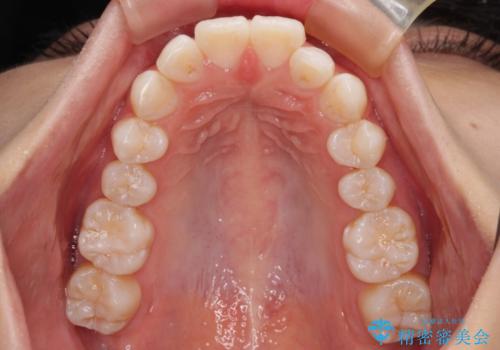

下唇に前歯が当たって跡が残ってしまう状態でしたが、スッキリとした口元に仕上げることができました。

下顎はデコボコが気になっていたため、上下左右第一小臼歯4本を抜去して、ワイヤー装置にて口元の突出感を改善するよう矯正治療を行うこととしました。